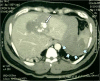

Background: Diagnosis of blunt abdominal trauma is a real challenge even for experienced trauma surgeons. Diagnostic tools that help the treating doctor in optimum management of blunt abdominal trauma include; Focussed Assessment Sonography for Trauma (FAST), Diagnostic peritoneal lavage (DPL) and CT scan.

Findings and conclusions: FAST is useful as the initial diagnostic tool for abdominal trauma to detect intraabdominal fluid. With proper training and understanding the limitations of ultrasound, the results of FAST can be optimized. DPL is indicated to diagnose suspected internal abdominal injury when ultrasound machine is not available, there is no trained person to perform FAST, or the results of FAST are equivocal or difficult to interpret in a haemodynamically unstable patient. In contrast, in haemodynamically stable patients the diagnostic modality of choice is CT with intravenous contrast. It is useful to detect free air and intraperitoneal fluid, delineate the extent of solid organ injury, detect retroperitoneal injuries, and help in the decision for conservative treatment. Helical CT is done rapidly which reduces the time the patient stays in the CT scan room. Furthermore, this improves sagittal and coronal reconstruction images which are useful for detecting ruptured diaphragm.